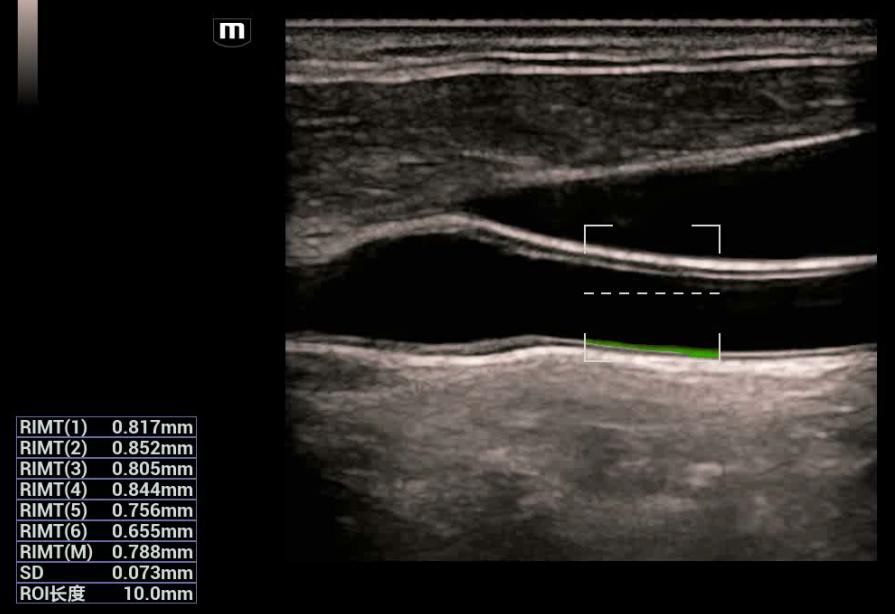

- RIMT - Rádiofrekvenčné meranie Intima Media

R-IMT

Rádiofrekvenčné hodnotenie a meranie IMT s vysokou presnosťou. RF-dáta merania IMT, obrazovo nezávislá automatická a mimoriadne presná IMT štatistika 6 kardiálnych tepov srdca v živom obraze.